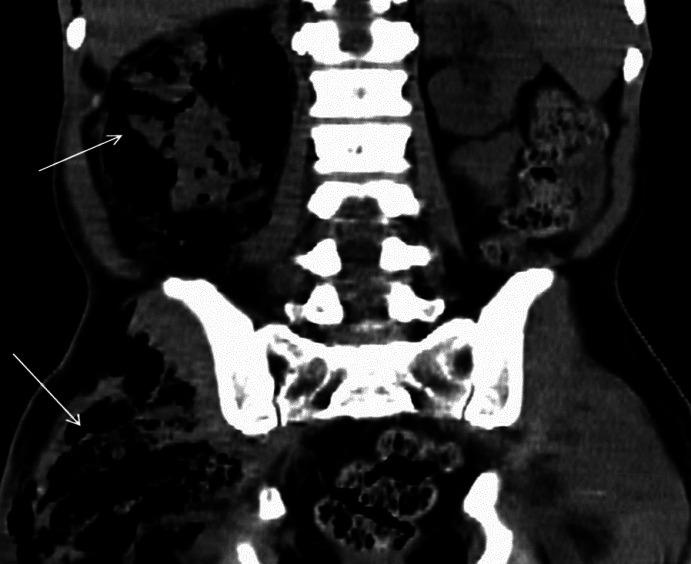

We present our experience of 22 cases of emphysematous pyelonephritis (EPN) treated from 1996 to 2012. Medical records were analyzed retrospectively for demographic profile, presence and duration of diabetes mellitus, and mode of clinical presentation. EPN was diagnosed based on demonstration of intra-renal gas by plain X-ray, ultrasound, and/or computed tomography (CT) scan. Details of medical treatment, reason for surgical intervention, and final outcome were recorded. Univariate analysis was performed to identify risk factors for mortality and P value of less than 0.05 was taken as significant. Twenty-two cases (6 males, 16 females) of EPN were diagnosed. Seven cases presented with acute pyelonephritis, seven cases with urosepsis, and the remaining eight patients with multi-organ dysfunction. CT grading of EPN was class IV in three, class III in four, class II in 14, and class I in one. All were initially managed medically with parenteral antibiotics. Ten patients needed additional surgical intervention. The overall survival rate was 86.3% (19/22). Among the risk factors analyzed higher CT grade, altered sensorium and thrombocytopenia were significantly associated with mortality. We conclude that a more conservative approach in managing EPN has become the standard of care. Patients having high CT grade of lesions (III and IV) with altered sensorium and thrombocytopenia at presentation are more likely to die due to the disease and may be better managed by an aggressive surgical plan.